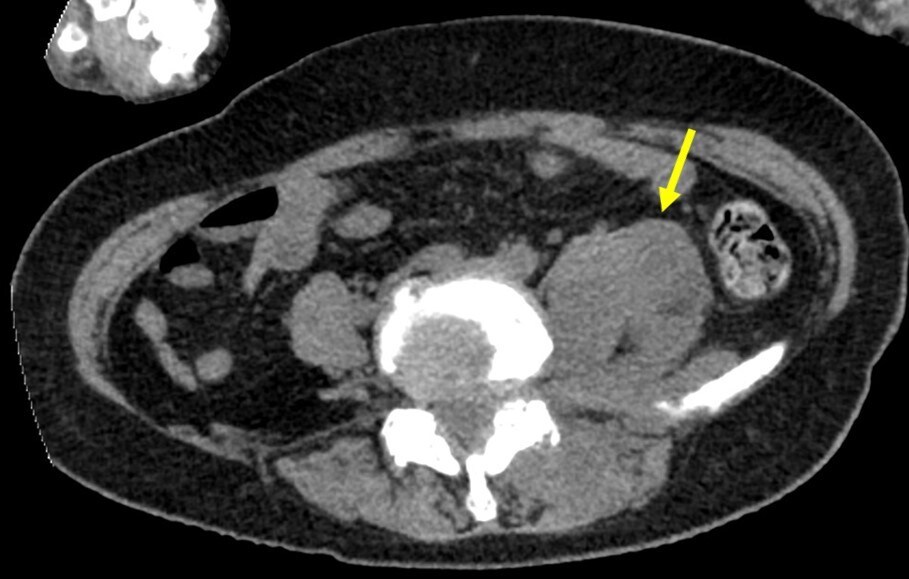

乳癌術後の再発・転移の検索目的で行われた単純CTで左腸腰筋膿瘍が疑われた。当科にCTガイド下ドレナージによる治療が依頼された。造影CTにて膿瘍は左大腰筋から左脊柱起立筋や左腰方形筋にかけて広範囲に認められた。形状は不整形で分葉状であり、辺縁に造影効果が認められ、内部は液体濃度の低吸収であり、隔壁も認められた。CTガイド下にドレナージカテーテルが膿瘍内に留置された。乳白色の膿汁がドレナージでき、ドレナージ後のCTでは膿瘍の縮小を認めた。

当該疾患の診断における造影CTの役割

腸腰筋腫大の鑑別疾患として、血腫や膿瘍が挙げられる。血腫は時期にもよるが単純CTで内部が高吸収となり、造影での増強効果が乏しいことが多い。一方、膿瘍は単純CTでは等吸収~低吸収を示し、内部にガスを伴うことがあり、造影で被膜が増強されるのが特徴である。

腸腰筋膿瘍の症状として、発熱、腰痛、psoas positionの三主徴が知られているが、実際に全てが揃う頻度は高くない。単純CTでは診断が困難な場合もあり、熱源不明で発見が遅れることもある。造影CTでは膿瘍が検出しやすくなり、さらにドレナージを行う上でも膿瘍腔の形状や範囲が確認できるため、非常に有用である。